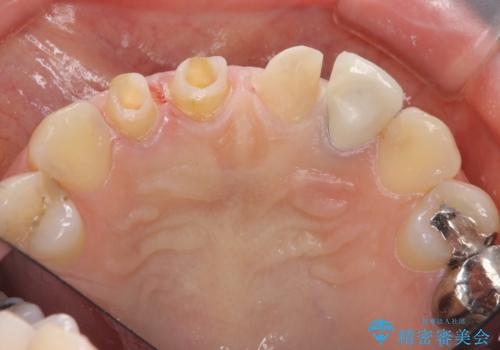

- 前歯を天然の歯のようにきれいにやりかえたいと希望され来院されました。

根尖病変の存在が判明したため、感染根管治療後にオールセラミックジルコニアクラウンを製作します。